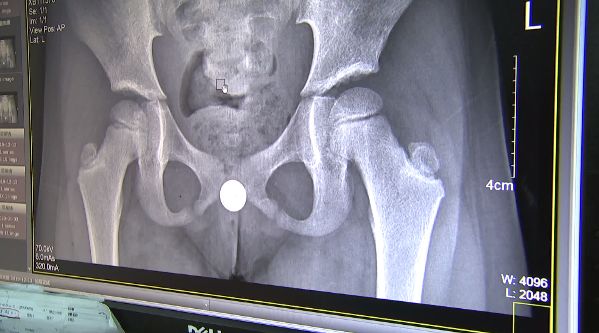

发现小姑娘下身有异物。

医生说,女孩*体下**是有一个纽扣电池。